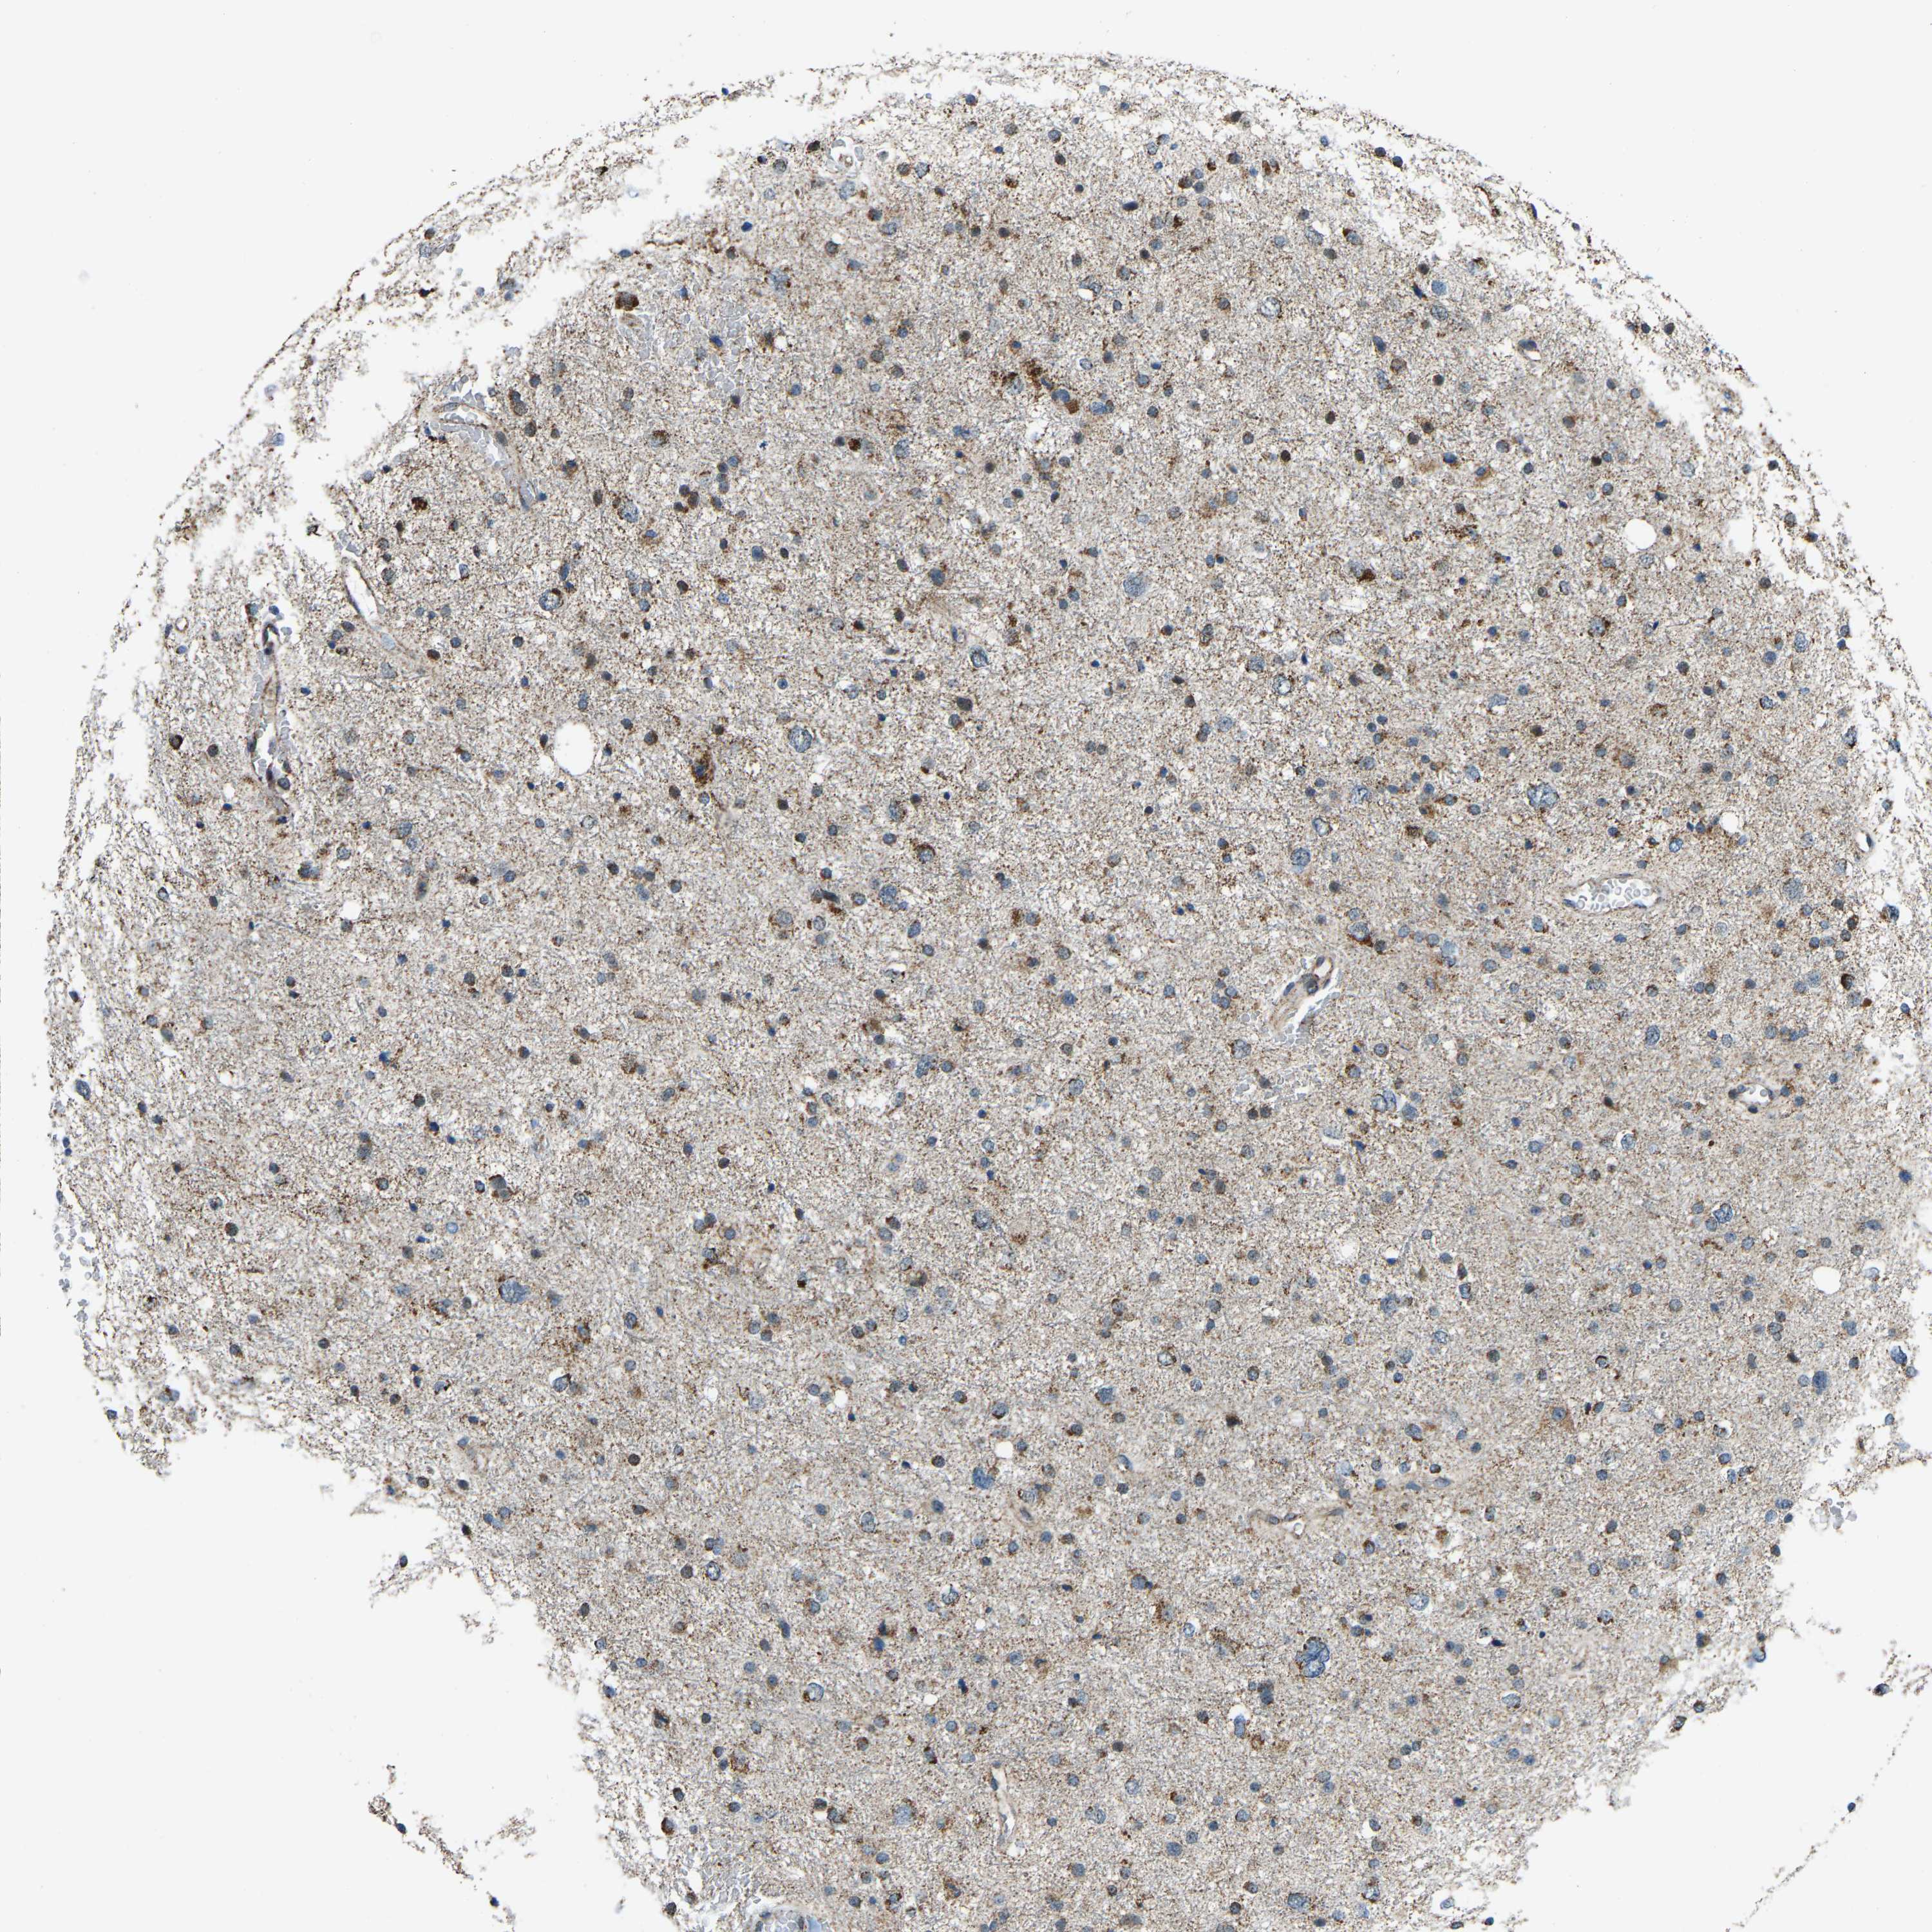

GLIOMA - Protein expressioni

A mouse-over function shows sample information and annotation data. Click on an image to view it in a full screen mode. Samples can be filtered based on level of antibody staining by selecting one or several of the following categories: high, medium, low and not detected. The assay and annotation is described here.

Note that samples used for immunohistochemistry by the Human Protein Atlas do not correspond to samples in the TCGA dataset.

Antibody stainingi

Antibody staining in the annotated cell types in the current human tissue is reported as not detected, low, medium, or high, based on conventional immunohistochemistry profiling in selected tissues. This score is based on the combination of the staining intensity and fraction of stained cells.

Each image is clickable and will lead to virtual microscopy that enables deeper exploration of all samples and also displays staining intensity scores, fraction scores and subcellular localization as well as patient and tissue information for each sample.

Antibody HPA019232

Antibody HPA021497

Antibody HPA021768

Staining

High

Medium

Low

Not detected

Intensity

Strong

Moderate

Weak

Negative

Quantity

>75%

75%-25%

<25%

None

Glioma, malignant, High grade

Glioma, malignant, Low grade